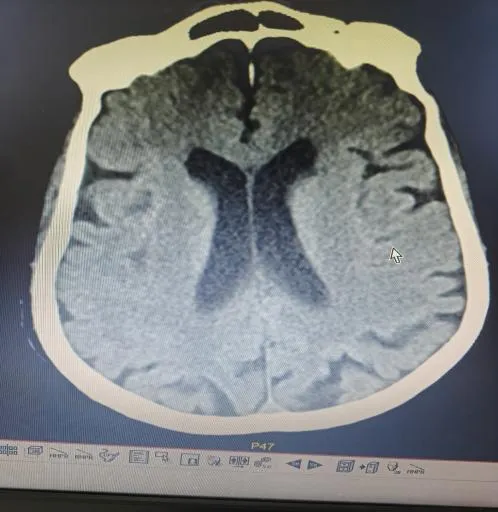

“时间就是大脑,每延迟一分钟,就有190万个神经细胞不可逆坏死!”面对紧急病情,医护团队争分夺秒。快速完成头颅CT等检查后,明确患者符合静脉溶栓指征且无绝对禁忌证,与家属协商签署溶栓同意书后,于22:04立即对患者进行阿替普酶溶栓治疗,DNT时间仅34分钟。然而,溶栓后复查影像学显示,患者大脑中动脉主干仍大血管闭塞,单纯溶栓未彻底开通血管,病情高危。关键时刻,救治团队当机立断,决定采用当前急性大血管闭塞性脑卒中的前沿救治方案——“溶栓桥接取栓”,为患者打通生命通道。

手术室内,神经内科张奕主任凭借丰富经验和精湛技术,在数字减影血管造影机引导下,经毫米级微创通道,将取栓器械精准送达闭塞血管核心部位。经不到1小时操作,成功完整取出堵塞血管的栓子,闭塞血管再通,脑部血供恢复。术后复查头颅 CT显示低灌注区脑组织全部存活。